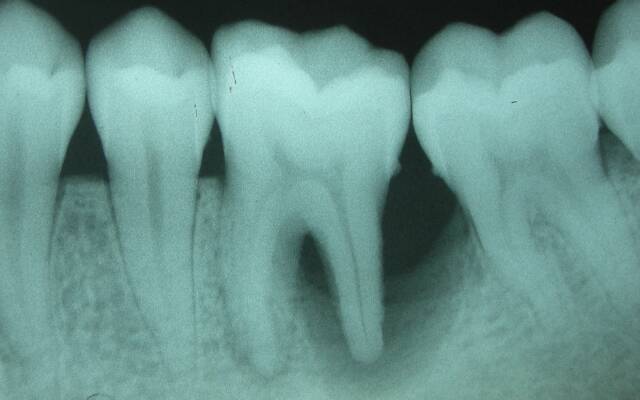

Для данной разновидности периодонтита зачастую характерно бессимптомное течение, что существенно затрудняет диагностику. Объективно выявляется изменение цвета коронки в результате нарушения трофики. Полость глубокая, а канал заполнен путридными массами с гнилостным запахом (они образуются при распаде пульпы). Зондирование и перкуссия безболезненны, а температурная реакция отсутствует. Основанием для постановки диагноза в данном случае является рентгенологическая картина.

На снимке определяется расширение периодонтальной щели в зоне апекса.

На рентгеновском снимке заметно изменение структуры цемента и дентина в области апекса и нечетко очерченный очаг разрежения костной ткани.

На снимке видно разрежение костной ткани с резкими отчетливыми контурами. По бокам от корня может иметь место гиперцементоз, а в области верхушки – деструкция твердых тканей.

Клиническими признаками являются постоянная боль, нарастающая при накусывании, отечность окружающих мягких тканей (в частности – сглаживание по переходной складке), их гиперемия, а также уплотнение и болезненность регионарных лимфоузлов. Симптоматика нарастает постепенно. Объективно определяется безболезненность при зондировании канала (он заполнен некротическими массами), резко положительная реакция при вертикальной перкуссии и умеренная болезненность при постукивании в горизонтальном направлении. Зуб может быть подвижен, и чаще всего он отличается по цвету от здоровых. Реакция на горячее и холодное – отрицательная. На рентгеновском снимке четко видны участки разрежения костной ткани с нерезкими контурами.